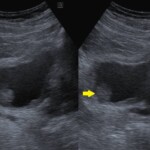

@腹部エコーで見つかった膀胱がん